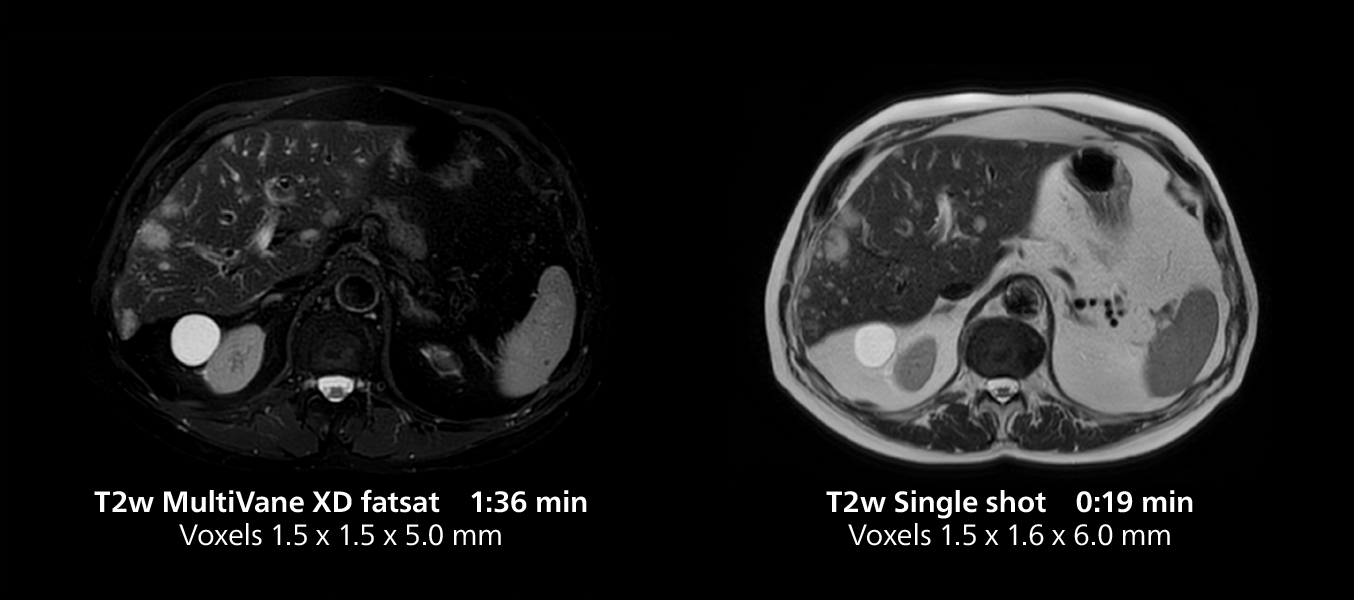

Liver imaging using MR 5300

This case includes 3D free breathing and 4D dynamic free breathing MRI of a metastasized liver. A high quality fatsat sequence with good resolution is obtained in 1:36 minutes with T2-weighted MultiVane XD.

Free-breathing scans provide reproducibility and patient comfort

Dr. Gellée highlights the robust free-breathing scans as “the feature that makes the biggest difference in my daily work. The 3D free breathing sequences are very reproducible, and the axial acquisition is very good. For example, in endometriosis, which is one of my focus areas, it provides high contrast and good resolution so that I can see small details. We also use free breathing for liver and pancreas imaging. In multi-phase liver studies, 4D Free Breathing delivers 3-second temporal resolution, making a dynamic scan with more than one arterial phase possible.”